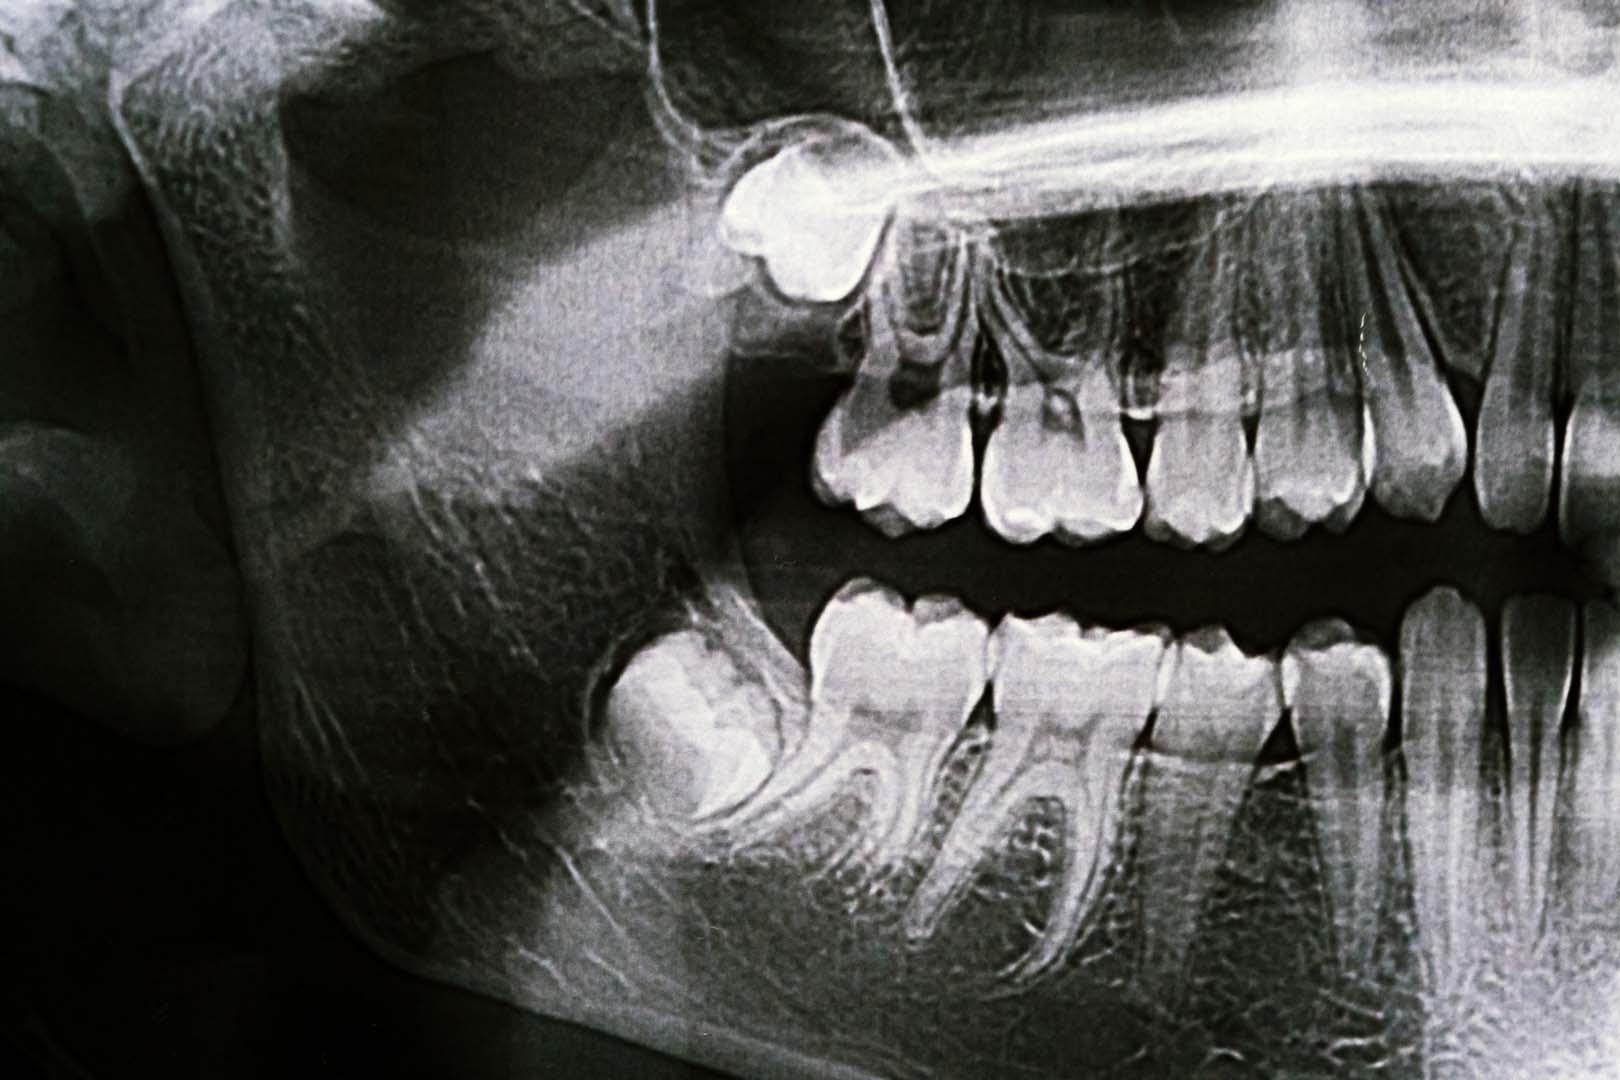

Türkiye'de diş hekimleri, 20 yaş dişi konusunda gençleri uyardı. 17 ile 21 yaş arasında genellikle sürmeye başlayan 20 yaş dişi, çenede yeterli alan bulunmaması nedeniyle çoğu kişide sorunlara yol açıyor. Modern beslenme alışkanlıkları ve yumuşak gıdaların etkisiyle, çene gelişimi yeterince desteklenmiyor. Bu durum, 20 yaş dişi için gereken alanın çoğu gençte oluşmamasına neden oluyor. Diş hekimleri, 20 yaş dişinin potansiyel sağlık riskleri taşıdığını ve zamanında müdahalenin önemini vurguluyor.

Uzmanlar, 20 yaş dişi geçmişte atalarımızda kaybedilen azı dişlerinin yerine yedek olarak geliştiğini belirtiyor. Ancak günümüzde, bu dişler çoğunlukla rahatsızlık, diş eti enfeksiyonu ve çürük riski nedeniyle çekiliyor. Diş hekimleri, ileride oluşabilecek sağlık sorunlarının önüne geçmek için 20 yaş dişi çekiminin genç yaşta yapılmasını tavsiye ediyor. Ayrıca, çenede yeterli alanı olan bireylerde dahi, 20 yaş dişi kısmi çıkma ya da çürük gibi komplikasyonlara yol açabiliyor. Bu nedenle, düzenli diş kontrolleri önem taşıyor.

20 yaş dişiyle ilgili problemler, sadece ağrı ile sınırlı kalmıyor; uzun vadede diş eti hastalıkları ve çevre dişlerde hasara neden olabiliyor. Diş hekimleri, 20 yaş dişi bulunan gençlerin düzenli olarak diş hekimi kontrolüne gitmesini öneriyor. Dişin varlığı, pozisyonu ve çene yapısına göre tedavi planı hazırlanıyor. 20 yaş dişinin gereksiz yere ağızda tutulması, hem çürük hem de enfeksiyon riskini artırıyor. Uzmanlar, 20 yaş dişiyle ilgili kararların mutlaka diş hekimi gözetiminde alınması gerektiğini belirtiyor. 20 yaş dişi sağlığının ihmal edilmesi, ilerleyen yıllarda daha ciddi ağız ve diş sağlığı sorunlarına yol açabiliyor.